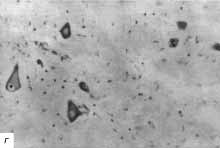

г - рядом с зоной сдавления рисунок строения сохранен, хотя и несколько

стерт, также выражен перицеллюлярный отек и дистрофические изменения нейронов;

ув. 400.

Проведенное морфологическое исследование подтвердило возникновение тяжелых

деструктивных изменений в веществе спинного мозга, развившихся в течение

3-х сут от момента сдавления дужкой шейного позвонка.

Наряду с этим морфологическое исследование выявило распространение ишемических

изменений как в проксимальных отделах спинного мозга, так и дистальных.

Причем, проксимальные отделы страдают в большей степени и на большем протяжении

по сравнению с дистальными. |